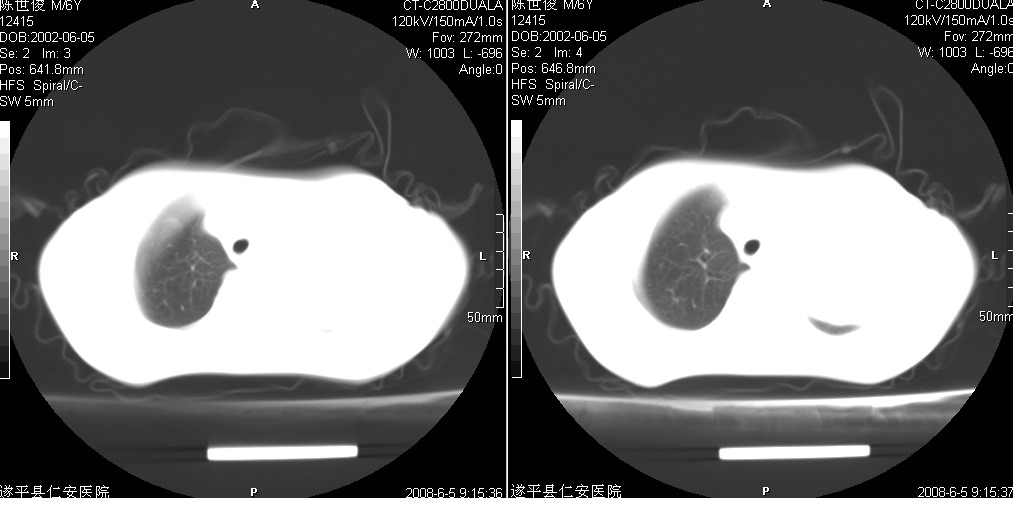

以下是引用xxhwh在2008-6-10 18:40:00的发言:[br]男,6岁,无规则发热一月余,体温在37.8——39度之间。一月前拍胸片示左上肺密度增高影,进行抗炎治疗8天,复查胸片未明显吸收。又改变抗菌素继续治疗半月,照胸片示病灶吸收不明显,行ct检查[br]征象:左上肺前段呈密实影,内可见支气管气像,远侧见絮状模糊影,中上纵隔左移。[br]意见:左上肺前段膨胀不全及感染,考虑为支气管异物或支气管内膜结核所致,[br]建议追问有无异物吸入史,行痰检及ppd检查